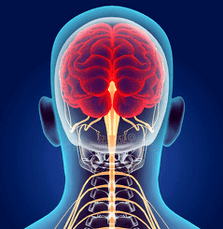

Vùng cổ nhỏ chứa nhiều ống thần kinh và mạch máu cung cấp cho não. Ở vùng cổ, các đốt sống khít chặt vào nhau hơn. Vì vậy, ngay cả với

Một thay đổi nhỏ ở một trong các đốt sống có thể gây chèn ép hoặc dịch chuyển dây thần kinh và mạch máu.

Một thay đổi nhỏ ở một trong các đốt sống có thể gây chèn ép hoặc dịch chuyển dây thần kinh và mạch máu.Do rối loạn tuần hoàn não, đau nửa đầu, loạn trương lực cơ thực vật và tăng huyết áp, các vấn đề về hệ tim mạch và hô hấp, thính giác, thị giác và phối hợp xảy ra. Ở dạng tiến triển, thoái hóa đốt sống cổ có thể dẫn đến hội chứng động mạch đốt sống. Động mạch đốt sống cung cấp máu cho hành não và tiểu não. Khi động mạch bị nén, tình trạng thiếu máu não và tủy sống có thể phát triển và đột quỵ cột sống có thể xảy ra.